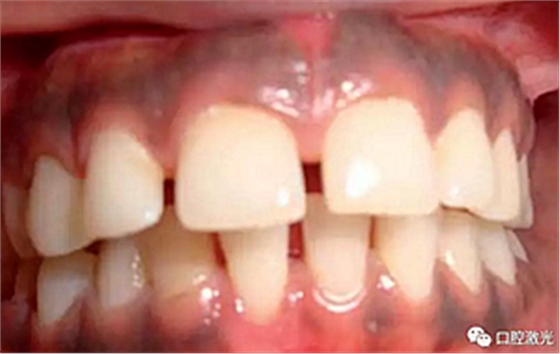

患者22岁,女性,主诉牙龈发黑。口腔检查显示牙龈部位呈黑色,但软组织健康,没有表皮粗糙或水肿现象。计划使用半导体激光进行治疗。手术前患者无需表麻或局麻。采用光纤接触方式,激光功率设定为1.5W至2W,连续模式。气化黑色牙龈区域上皮组织。不断重复该过程,直至足够深度的牙龈软组织表皮被去除干净。患者术后需采用漱口水进行口腔护理。

术中